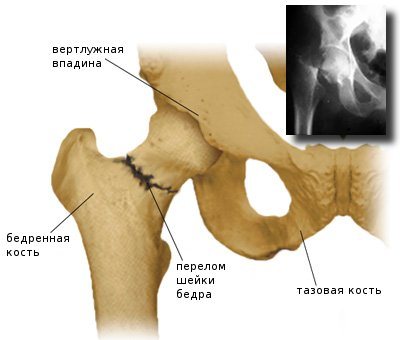

Перелом шейки бедра

Перелом плечевой кости (рентгенограмма)